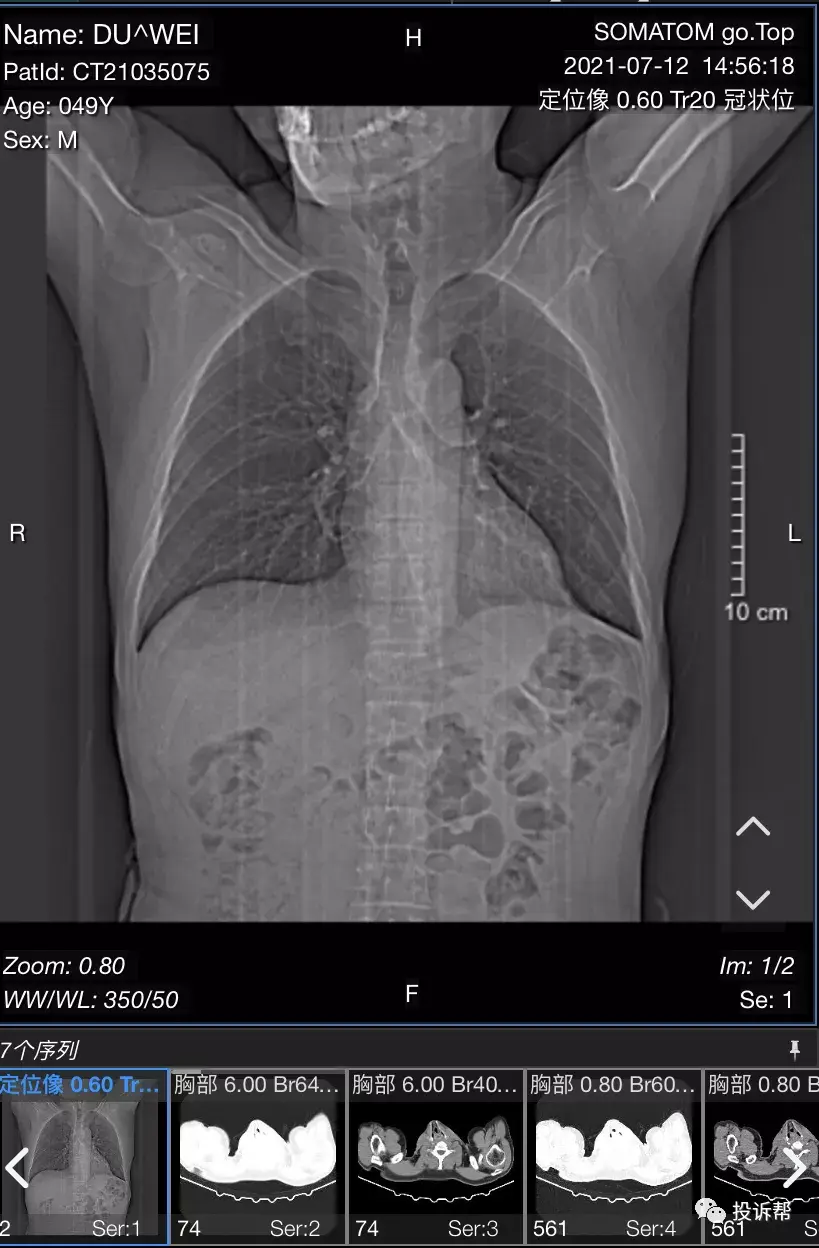

杜先生通过投诉帮的豹料云系统,上传了自己的CT三维重建影像。

“三维重建的(影像)可以看到已经把脊柱拉直了,脊柱应该是S形弯曲,因为膈肌脚拉长了之后把脊柱顶着。”